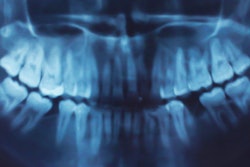

Panoramic x-rays can help practitioners better predict maxillary canine impaction, according to a new study in the American Journal of Orthodontics and Dentofacial Orthopedics (July 2012, Vol. 142:1, pp. 45-51).

"Diagnosis of maxillary canine impaction is possible at 8 years of age by using geometric measurements on panoramic radiographs," the study authors concluded.